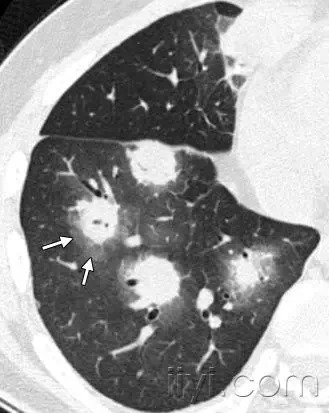

晕征 医学百科网 | YxBaike.Com

医学百科网 | YxBaike.Com

CT扫描:晕征是CT上结节或者肿块边缘的磨玻璃影。首先被描述为侵袭性曲菌病边缘的出血征象。实际上晕征是非特异性的,可以见于其它类型结节所致的出血,或者肿瘤的局部肺浸润。(例如腺癌)